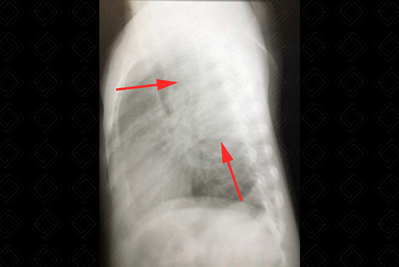

Texto alternativo para a imagem Figura 2. Créditos: Dra. Elazir Mota - Rio de Janeiro/RJ

Descrição das figuras 2 e 3: Massa em mediastino posterior, compatível com neurofibroma em paciente portador de neurofibromatose tipo 1.

• O mediastino posterior contém as seguintes estruturas: gânglios simpáticos, cadeias parassimpáticas, linfonodos, nervos, ducto torácico, aorta descendente, pequenos vasos e vértebras. A maioria das lesões possuem natureza neurogênica (eles podem ter origem do sistema nervoso simpático, como neuroblastoma , ou dos nervos, como neurofibroma ou schwannoma ) (figuras 2 e 3).